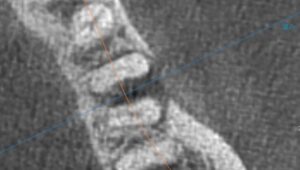

【近心根と分岐部に透過像がある】

【黄色矢印が透過像】